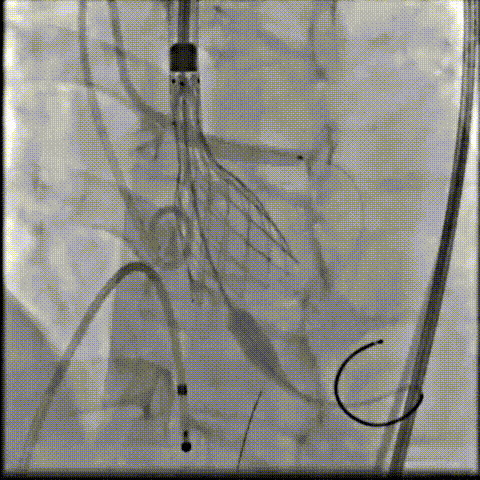

术中影像

根部造影可见返流;20mm球囊预扩,LCA灌注缝隙狭小

预置LCA保护;第一次释放,

团状钙化挤压导致瓣膜(AV23)少量下滑

回收后重新定位,第二次释放,

瓣膜(AV23)深度仍未达到最佳预期

完全回收,第三次定位释放,瓣膜(AV23)位置良好

瓣膜工作位释放“烟囱支架”;

瓣膜(AV23)完全释放后,“烟囱支架”后扩

最终造影,“烟囱支架”显影清晰,瓣膜形态及LCA灌注良好